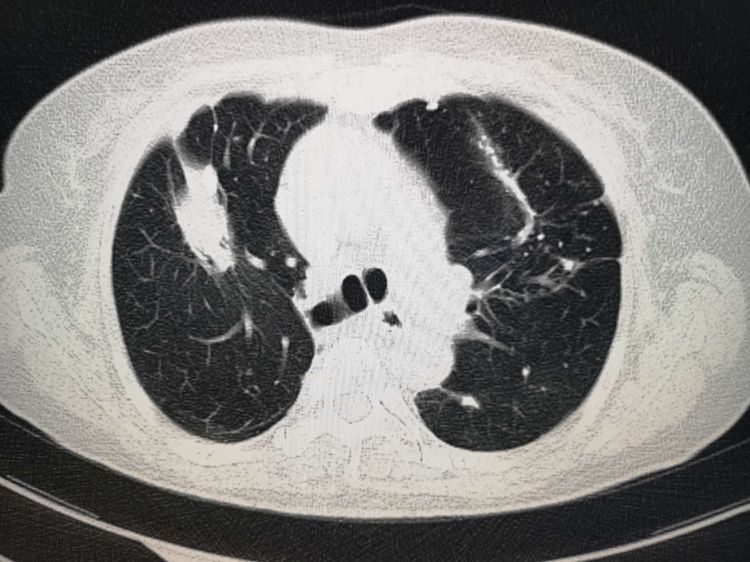

一位60多岁的老妇人,年轻时得过肺结核,每年胸部X光片体检,都是陈旧性肺结核表现:

有一次因为右边肩膀疼来做肺部CT,结果查出肺癌,晚期了:

右上肺这个肿块,围在多发的陈旧性结核灶之间,悄悄长大了!并且发生了纵隔、锁骨上多发淋巴结转移……

如果她早一点选用胸部CT检查,结局会不会不同呢?肯定会!

后面这个老妇人虽然不能手术了,但肺癌的治疗方法,最近几年进步很快,包括靶向治疗、射频消融治疗、放射性粒子植入、放化疗为主的综合治疗等,长期带瘤生存的病人越来越多了。

她一年半后来复查的时候,肿瘤缩小了很多: